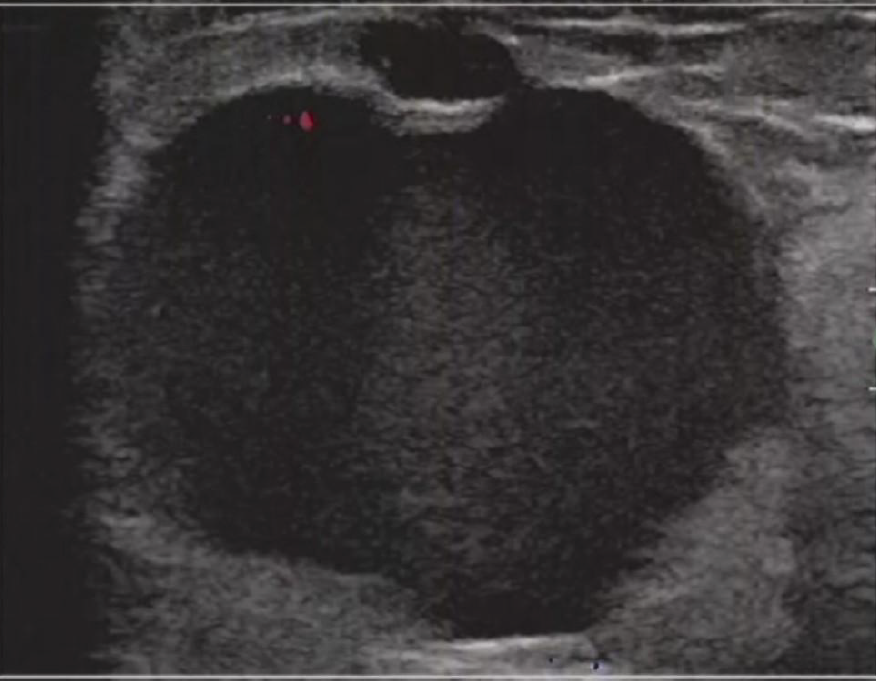

它怕“伪装高手”。 有些早期癌长得特别“面善”,在B超屏幕上边缘光滑,和最常见的良性结节——纤维腺瘤——简直是双胞胎。侦探路过一看:“哟,良民,放行!”结果就错过了。直到它长出了新的可疑特征,或者旁边又冒出了新的“同伙”,才引起警惕。

这名患者彩超结节很光滑,彩超判定为BIRADS2类,但术后病理证实为乳腺癌